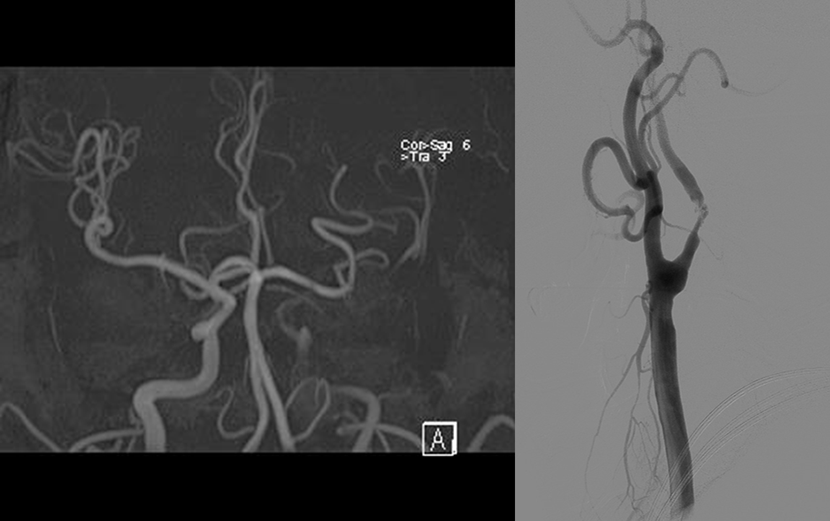

뇌MRA 와 뇌혈관조영술에서 좌측내경동맥의 심한 협착이 보임

성형술과 스텐트 삽입술을 시행하여, 우측의 수술전 사진과 비교시, 혈관을 넓혀주어 추가적인 뇌경색을 예방